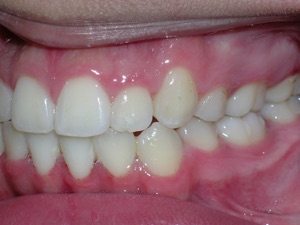

Here’s an example from a young boy who had very significant crowding. One can see that the canines on top and bottom are blocked out. There was also an overbite. The combination made the case challenging. Watch.